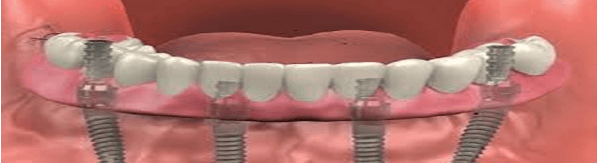

Dental restoration has undergone an advancement because to all-on-4 dental implants, which provide people who were missing most or all of…

For people who are missing the majority or all of their wisdom teeth, a whole mouth dental implant operation is frequently…